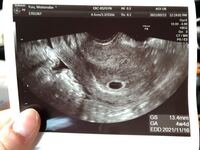

妊娠6週3日 6w3d の超音波 エコー 写真